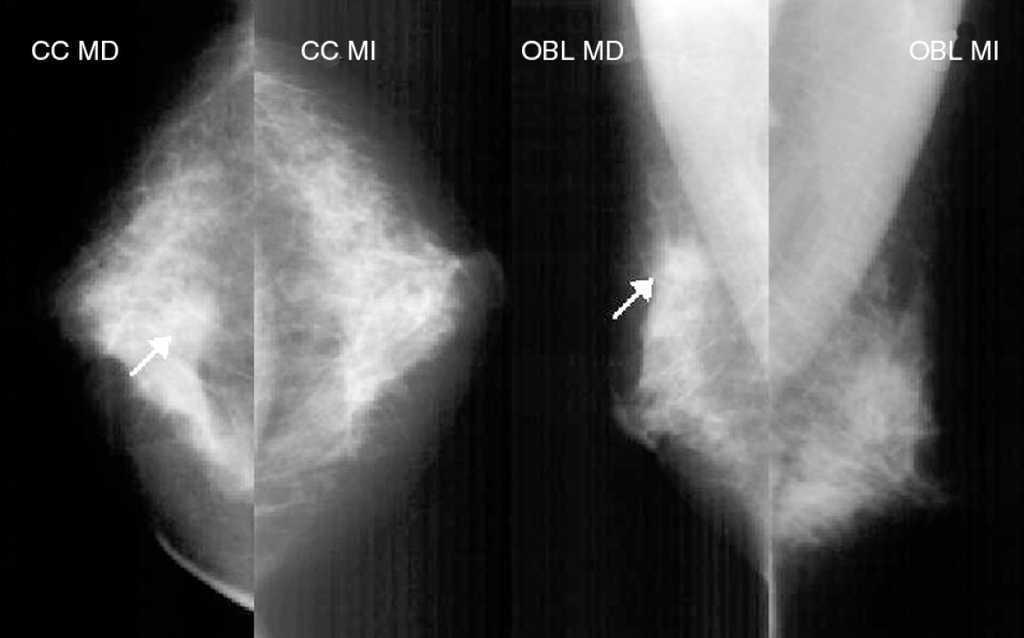

Ante la sospecha de neoplasia mamaria en MD se solicita la realización de una mamografía, ecografía y RM bilaterales. La mamografía muestra unas mamas con tejido fibroglandular de predominio denso con un nódulo espiculado de aproximadamente 1 cm en la LICS de MD. No se aprecian lesiones en MI (fig. 1). La ecografía bilateral confirma la presencia de un nódulo sólido de 1 cm con bordes irregulares, que coincide con la tumoración palpable en la LICS de MD. El estudio de MI no presenta hallazgos significativos (fig. 2). La RM bilateral informa de «... lesión nodular espiculada en LICS de MD con patrón de captación sugestivo de malignidad y que se extiende caudalmente a través de la línea intercuadrántica en presencia de pequeños nódulos satélites con patrones de captación similares que se aproximan hacia el pezón». La lesión nodular principal alcanza unos 14 mm de diámetro mayor, mientras que el conjunto de las lesiones satélites alcanzan unos 15 mm. En MI, «... captaciones significativas en fase arterial con presencia de un pequeño nódulo mal delimitado con un patrón de captación sugestivo de malignidad y con pequeñas lesiones satélite que se extienden caudalmente al igual que en la MD». Estas lesiones están en el cuadrante inferoexterno (CIE), en proximidad de la línea intercuadrántica inferior, a unos 2,5 cm del pezón (fig. 3). Ante el hallazgo de un área sospechosa en la RM de MI se decide solicitar una mamografía magnificada de cuadrantes inferiores de MI, que es informada como normal (fig. 4). Se decide biopsiar con aguja gruesa la masa de MD, y el resultado es de carcinoma ductal infiltrante (CDI) de grado 2.

Figura 1. Mamografía bilateral. Mamas con tejido fibroglandular de predominio denso con una imagen espiculada de aproximadamente 1 cm en la línea intercuadrántica superior de la mama derecha (flecha).